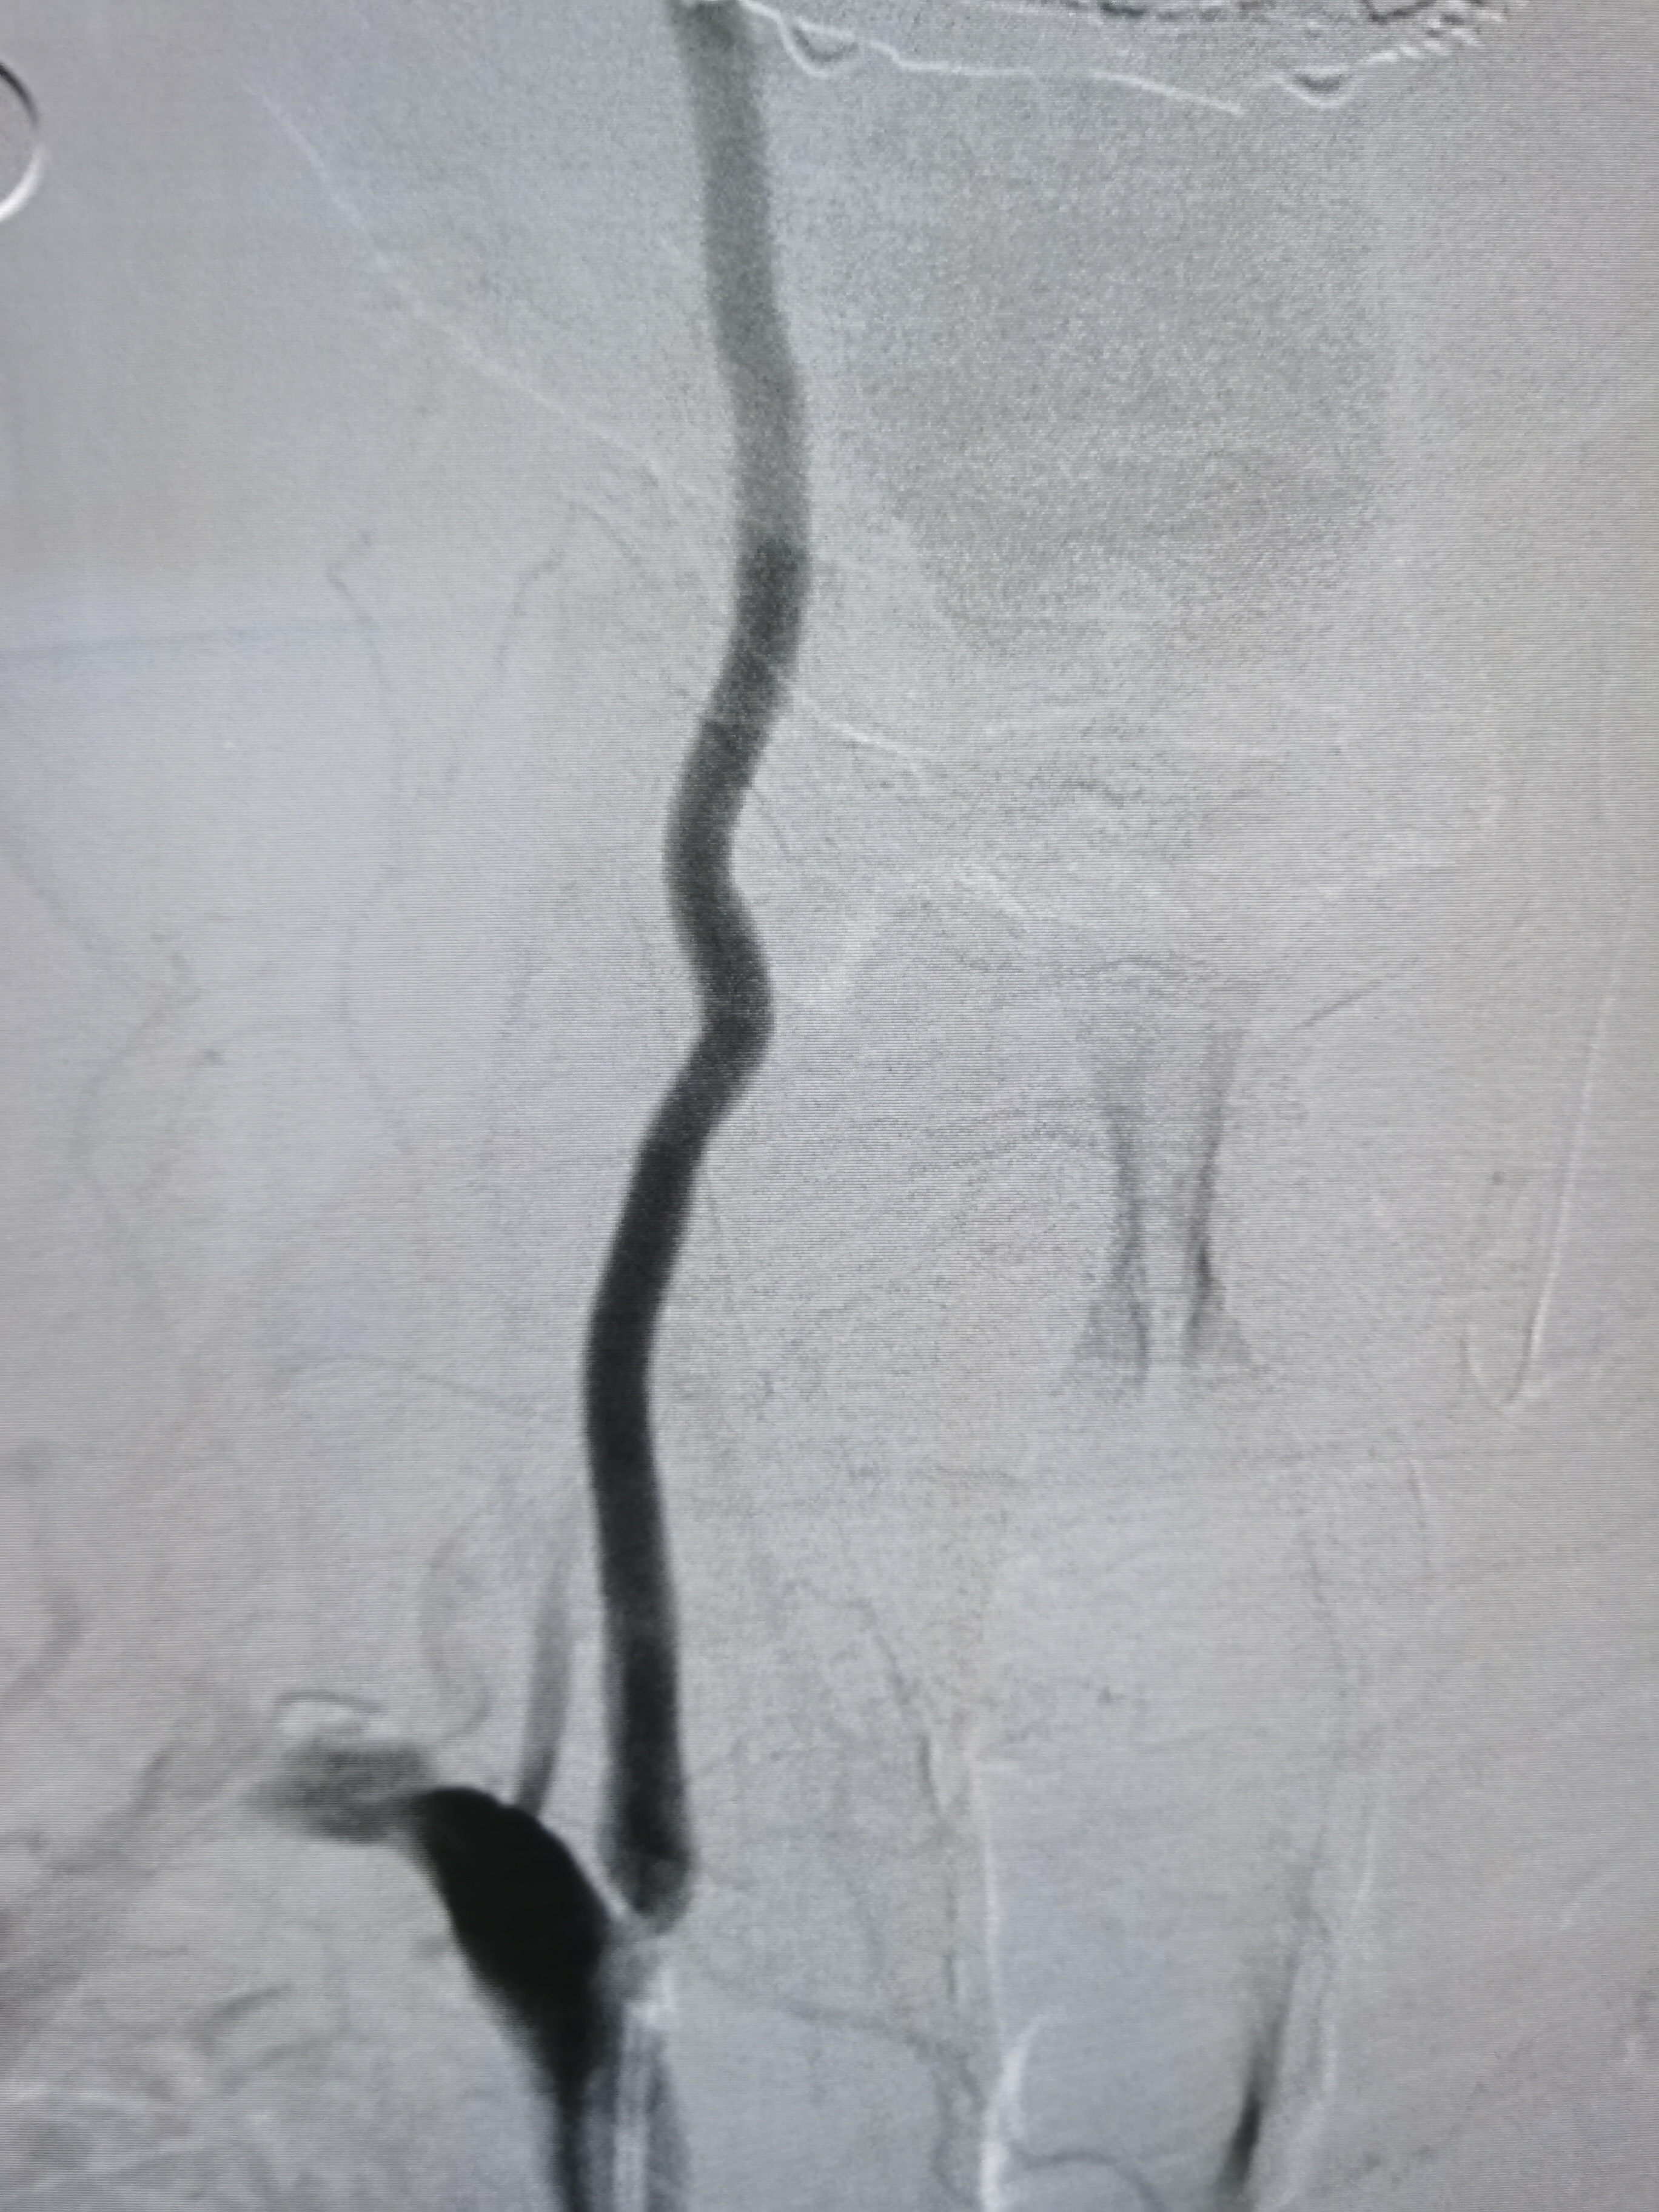

5.0/15支架定位

支架释放后狭窄解除